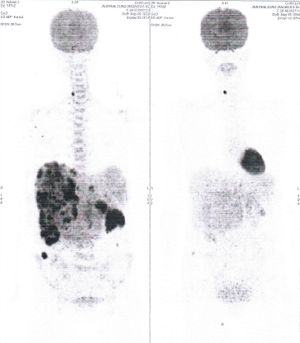

Below are some of the cases, from more than 80 cases we have treated so far with good results. When reading the PET/CT scans, the picture on the left is before treatment, and the picture on the right is after treatment. The intensity of black represents the activity of the cancer, but some black areas are not cancer: brain, heart, radioactive urine in bladder. For the heart, the intensity of black depends on the number of hours of fasting: if more than 10 hours, the heart is not even black, but if fasting is less than 6 hours, it is very black. The intensity of black in the brain can be variable in different scans depending on the brain activity at the time of the scan. The intensity of black in the radioactive urine can also be variable due to the hydration of patients and the time of injection of diuretic.

CASE NO: 1

(HEPATOCELLULAR CARCINOMA + STOMACH CANCER)

A middle-aged women who is very thin and very weak, can hardly walk, lying in bed most of the time. She saw a cancer specialist in a top hospital who discovered that she had massive hepatocellular carcinoma, and another cancer in the stomach. Given that hepatocellular carcinoma is incurable and stomach cancer is very difficult if not impossible to cure without surgery, she was told that nothing could be done for her. She came to ask us to help her. After just 4 treatment, the hepatocellular carcinoma went into remission, and the stomach cancer (arrow) became less active. Until today, more than 6 months later, the hepatocellular carcinoma is still in remission.